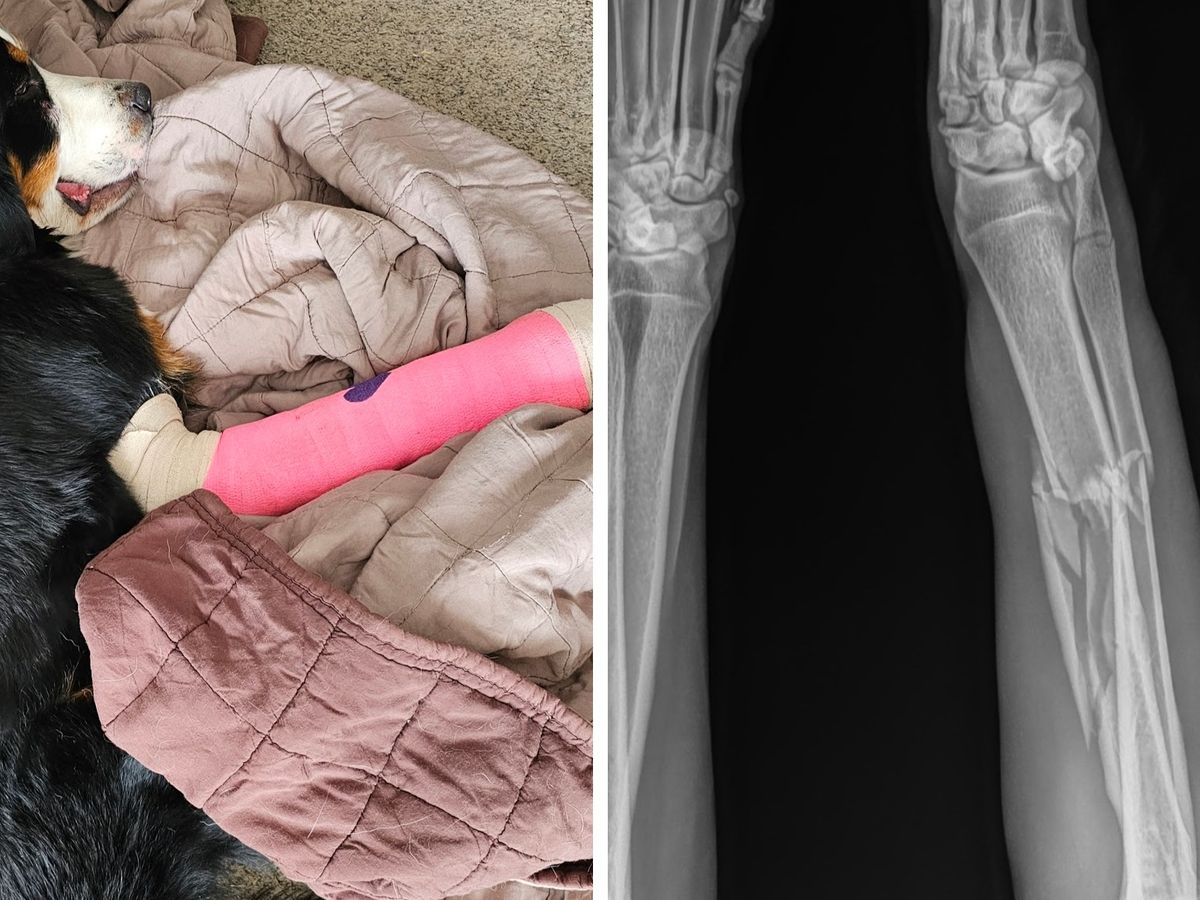

“Two people found her at the top of Meyer Ranch open space with a broken leg. One kind man carried her off a cliff top and onto stable ground. He ran down to meet animal control and park rangers while the other stayed near the dog. We were hiking by and talked to the woman waiting with the dog, now hiding in the bushes. On the trail down, we bumped into the man, park rangers, and animal control hiking back up. Presumably, the dog was carried out by this team. Such kind people to call for resources and and [sic] make sure this doggy was rescued.

Nova’s ordeal is not yet over.  Her leg will need surgery and may possibly need to be amputated.  Any amount you can contribute to help with Nova's medical bills is appreciated.